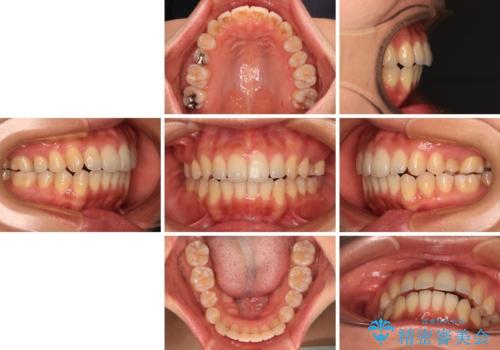

ワイヤー装置にてある程度歯列が改善されたところで、上下をインビザラインにて矯正治療を行うこととしました。

舌のトレーニングをしっかりと行ってくださり、前歯部のオープンバイトは大幅に改善されました。

もう少しでよりタイトに前歯が接触できそうでしたが、患者様がもう十分とのことで治療を終了しました。